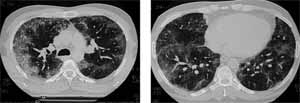

Por los hallazgos clínicos y paraclínicos, además de los síntomas crónicos y persistentes previos al ingreso, se sospechó una enfermedad pulmonar crónica. Se realizó estudio mediante tomografía de tórax.

Figura 5. Tomografía donde se observan infiltrados de ocupación alveolar, los cuales comprometen principalmente la língula.

Dos meses después de su egreso se realizó una tomografía de control en la cual se evidenció resolución de los infiltrados. Sin embargo, al disminuir los esteroides se observó en una nueva tomografía, reaparición de infiltrados (Ver figura Nº6), por lo cual se prescribieron corticoides crónicamente y se diagnostico una neumonía eosinofílica crónica.

Figura 6. Tomografía con focos predominantemente periféricos subpleurales sin distribución segmentaria. Infiltrados mixtos en segmento medial de lóbulo medio.